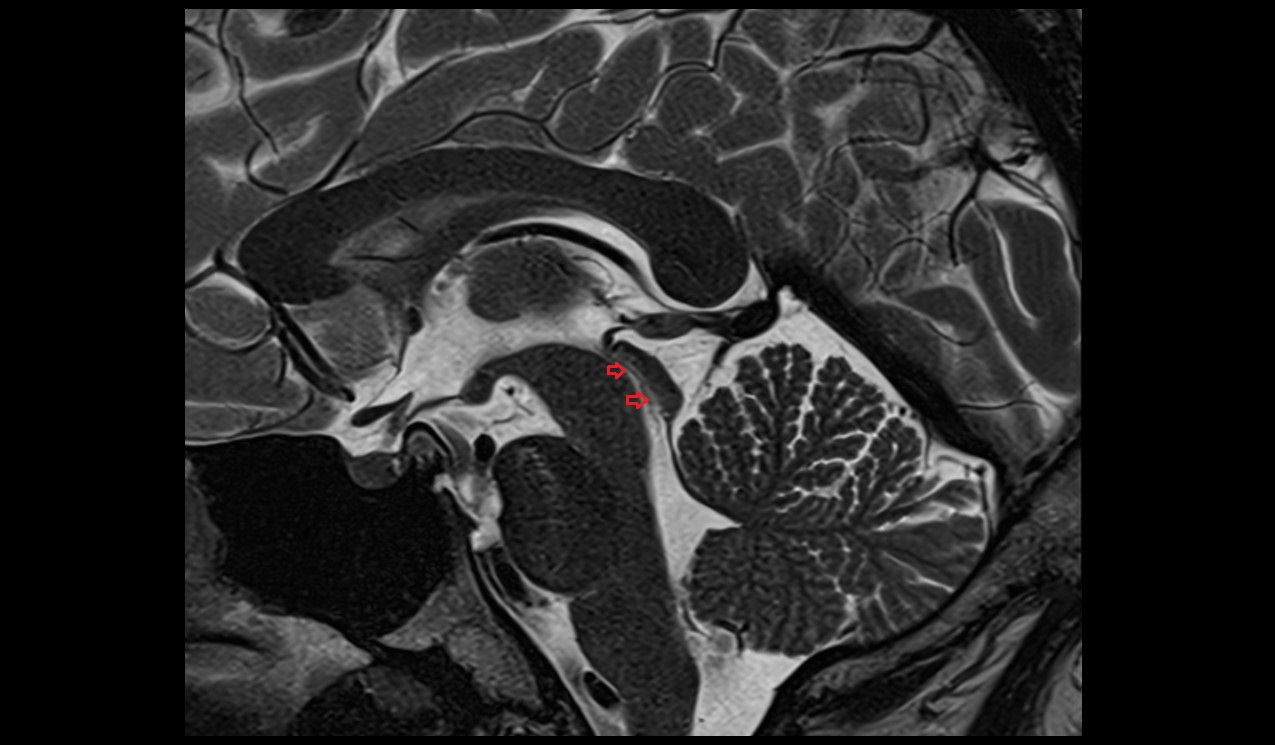

- Median aperture of fourth ventricle (foramen of Magendie)

- Lateral aperture of fourth ventricle (foramen of Luschka)

- Cerebral aqueduct